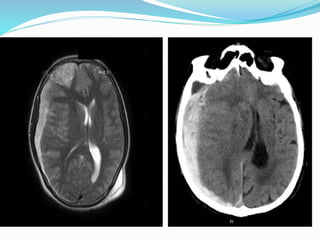

Diagnostic evaluation

 CT scan is initial investigation of choice

 After 2 weeks it will appear as isodense

 After 3 weeks it will assume a lenticular shape &

hypodense in relation to brain

 In case acute on chronic SDH ,it may appear as mixture of

hypodense & hyperdense material

 Sometimes its difficult to distinguish between brain

parenchyma & chronic SDH ,in this case contrast

material 300 ml of 30 % diatrizoate meglumine is

used which cause membranes of isodense hematoma to

opacify.

 Chronic SDH

 T1: if the haematoma is stable it appears isointense to

CSF, it can appear hyperintense to CSF if there is a

rebleed or infection.

 T2: if haematoma is stable it appears isointense to CSF

if there is rebleed the haematoma appears hypointense

 FLAIR: hyperintense to CSF

 Rarely, the periphery of the SDH may calcify,

see calcified chronic subdural haematomafor an in-

depth discussion regarding the MRI signal

characteristics of this entity.

Diagnostic evaluation  CTscan is initial investigation of choice  After 2 weeks it will appear as isodense  After 3 weeks it will assume a lenticular shape & hypodense in relation to brain  In case acute on chronic SDH ,it may appear as mixture of hypodense & hyperdense material  Sometimes its difficult to distinguish between brain parenchyma & chronic SDH ,in this case contrast material 300 ml of 30 % diatrizoate meglumine is used which cause membranes of isodense hematoma to opacify.

 Chronic SDH T1: if the haematoma is stable it appears isointense to CSF, it can appear hyperintense to CSF if there is a rebleed or infection.  T2: if haematoma is stable it appears isointense to CSF if there is rebleed the haematoma appears hypointense  FLAIR: hyperintense to CSF  Rarely, the periphery of the SDH may calcify, see calcified chronic subdural haematomafor an in- depth discussion regarding the MRI signal characteristics of this entity.